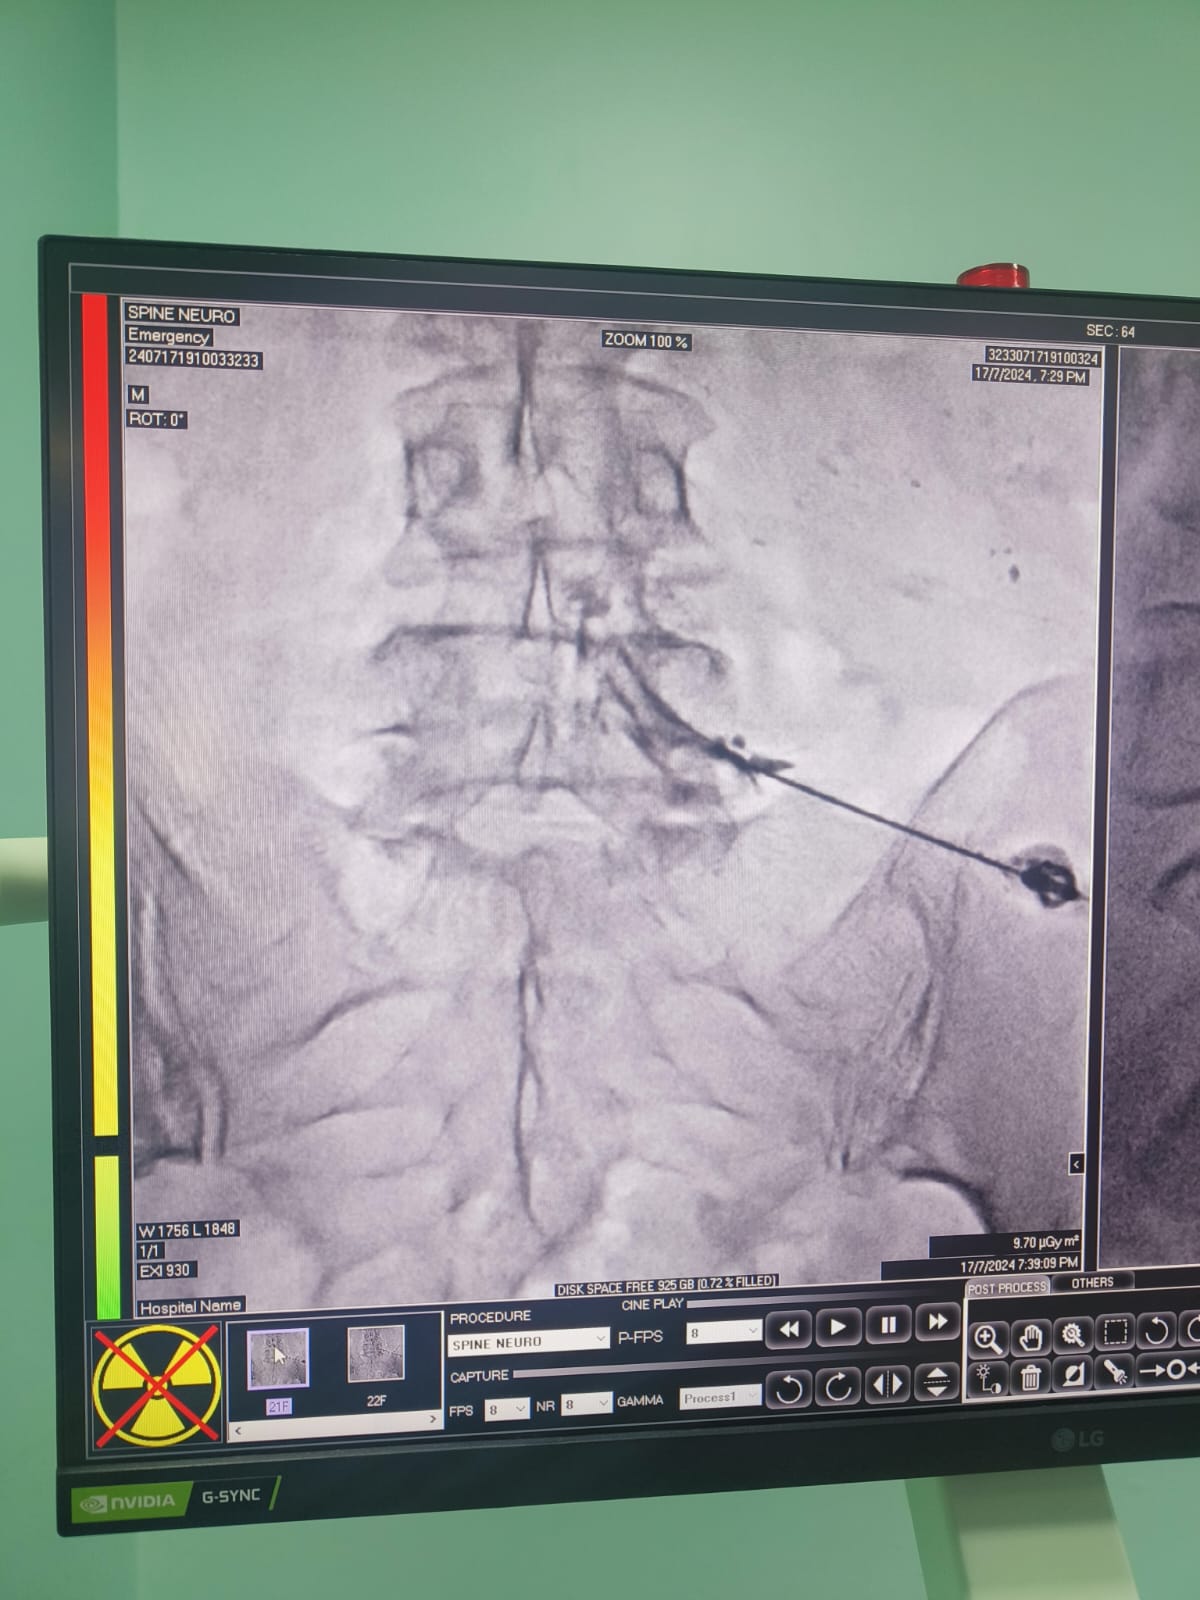

Vascular Neuro Intervention